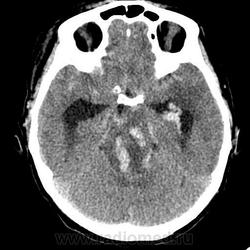

КТ головного мозга, кровоизлияние.

"Скорая" привезла женщину 75 лет, найденную на улице. На КТ направлена с д-зом: кома неясного происхождения. Вот такая картина на КТ.

Острое внутримозговое кровоизлияние с выходом крови в желудочки (боковые - сгустки преимущественно в левом + эффект седиментации с горизонтальным уровнем жидкость\жидкость в задних рогах; сгустки крови в третьем желудочке, кровь в четвертом). Значительное увеличение височных рогов боковых желудочков - гидроцефалия. Смешение срединных структур вправо, отек белого вещества перивентрикулярно слева.

Довольно большие кровоизлияния в стволе мозга (что объясняет тяжесть состояния).

Дифференциация серого и белого в-ва сохраняется, хотя субарахноидальное пространство не прослеживается - проявление масс-эффекта, начальный этап отека мозга.

Остается вопрос по слегка гиперденсному (относительно серго вещества) однородному фокусу в левой лобной доле... и по причине кровоизлияния. Что касается последнего могу предположить патологию базилярной артерии (разрыв аневризмы?)... правда не вижу что-то крови в цистернах основания черепа.

Я написала отек мозга, острое массивное (около 100 мл только внутримозговое) смешанное кровоизлияние слева + в стволе, с прорывом и гемотампонадой желудочков, выраженной латеральной дислокацией (13 мм), менингиома? лобного полюса слева. Убедительных данных за опухоль, давшую кровоизлияние, не вижу, хотя такая мысль тоже была.  Контрастировать такую пациентку никто не будет, агонизирующая(.

У, сколько всего написано. Пока не пришла Nela, поучаствую и я. 1. Кровоизлияние в ткань мозга, а не в опухоль: а)не видно ткани опухоли; б) неясна первичная локализация опухоли (левые базальные ядра?!); в)нет перифокального отека вокруг предролагаемой опухоли, г) при опухолях прорывы в желудочки - редкость; 2) к поперечной дислокации добавил бы безесловную аксиальную: даже цистерна моста сужена, не говоря уже про обходную-четверохолмную и другие; 3) менингиома в левой лобной области, на мой взгляд, сомнительна (кстати, покажите ее пожалуйста), ИМХО - "игра" плотностей;  4) ///метастазы в сосудистые сплетения/// - это очень круто, но они не дали бы внутримозгового кровоизлияния, как и ///плексуспапилома///.

Массивное медиальное кровоизлияние с прорывом в желудочки. Кровоизлияние в ствол. Признаки вклинения. В лбу может что-то и есть, но это не принципиально. А может быть и отечные извилины. Смущает, что нет масс-эффекта.

Про отек: субарахноидальных щелей совсем нет, по белому веществу и в стволе снижение плотности, извилины утолщены, серое вещество на этом фоне выглядит более светлым, толстым, подушкообразным.

Причина таких кровоизлияний, как правило, гипертензия и атеросклероз.

Кровоизлияние не связанное с объемным образованием, "гипертоническое", основной массой - в области базальных ядер, кровоизлияние в ствол мозга, кома ясного происхождения :) А менингиома менигниомой, не мешает, так сказать.  Отека мозга здесь небольшой, больше выражено набухание.